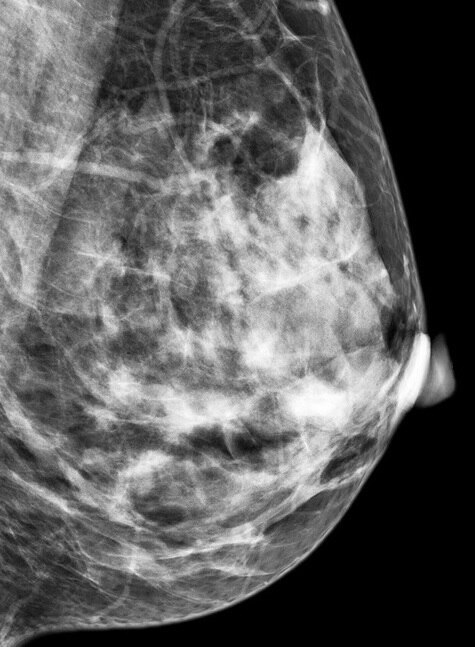

You can't see or feel these in a clinical exam, but a mammogram can help measure and compare the different types of breast tissue. You can learn more about what it looks like in the charts below.

Radiologists are able to use this to score breast density on a scale from very low density to mostly dense.

As you can see from the slider below, dense breasts can also make a mammogram more difficult to interpret.

This is what cancer looks like on a mammogram with a woman who has low density breasts. / While in dense breasts, cancer can be harder to spot (Photos: BreastScreen SA).

Cancers can be masked by the glandular and connective breast tissue, which all show up as white on a mammogram (compared to fatty tissue, for example, which appears as dark areas).

A close up image of a fatty breast. / In very dense breasts, glandular and connective breast tissue appear prominently on a mammogram (photos supplied by Dr Alia Kaderbhai).